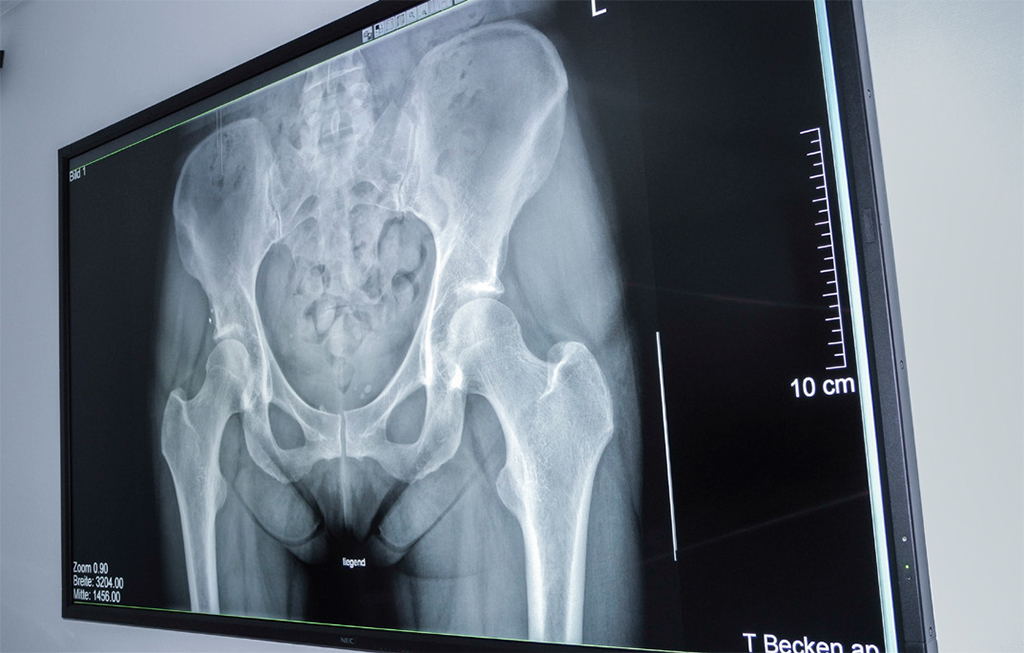

El hospital Merian Iselin para ortopedia y cirugía es uno de los tres centros sanitarios privados más grandes de Basilea (Suiza) y donde se realiza el mayor número de intervenciones quirúrgicas de rodilla y cadera. El departamento de radiología es el elemento neurálgico de esta institución, donde se crean informes de imagen para los médicos externos e internos. Más de 20.000 exámenes radiológicos se llevaron a cabo en 2014.

«La medicina moderna es un trabajo en equipo. Todo funciona mejor si se pueden evaluar y discutir los resultados con los médicos involucrados y los pacientes. Para este propósito, la visualización de la imagen es clave. Tiene que permitir que se vea desde diferentes ángulos y distancias en la sala para llevar a cabo y obtener un análisis profundo».

Estos equipos funcionan como pantallas de diagnóstico y cumplen los requisitos para soluciones MDT, ya que cuentan con resolución 4K UHD, precisión en el color y procesamiento de señales. Estos equipos permiten al hospital Merian Iselin ofrecer valoraciones más exactas desde diferentes ángulos y distancias de visión, algo fundamental para diagnósticos grupales.

En el hospital, el NEC X841UHD de 84 pulgadas tiene una pantalla que mide más de dos metros de diagonal y cuenta con modo Dicom para analizar las radiografías en la sala de conferencia médicas.

«Con la nueva resolución de la sala de conferencias el trabajo diagnóstico puede ser visualizado, lo que aumenta la credibilidad de las conclusiones al permitir ver las lesiones de manera más exacta”, añade Egelhof. Esto supone menos incertidumbre para todos los involucrados y aumenta la productividad tanto en radiología como en otras especialidades médicas.